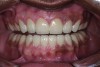

Figure 19. Postoperative frontal smile.

Figure 19

The final restorations depicted restoration of form, function, and beauty, with good harmony of restoration and the periodontium (Figure 19 through Figure 25). MIP was in harmony with CR, and right and left lateral excursion discluded all posteriors with anterior group function. The postoperative orthopantomogram (OPG) (Figure 26) shows the treatment done while maintaining the vitality of anterior teeth.